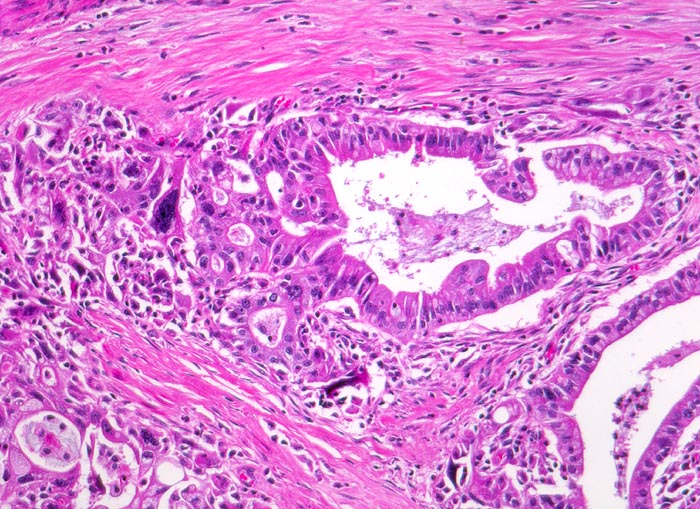

duktales Adenokarzinom des Pankreas

Teils kribriforme Tumordrüsen mit ausgeprägten Zellatypien und Kerngrössenschwankungen. Ein Teil der Drüsenlumina enthält nekrotische Tumorzellen. Die Tumorinfiltrate liegen eingebettet in reichlich desmoplastisches Stroma.

Unscharf begrenzter weisser derber Herd im Pankreaskopfbereich. Stenosierung und praestenotische Dilatation von Ductus choledochus und Pankreasgang vor der Papille.

Zunehmender schmerzloser Ikterus. Sonographische Darstellung einer 4cm grossen echoarmen Raumforderung im Pankreaskopfbereich. Dilatation des Pankreasganges und des Ductus choledochus. Whipple Operation.

Histologie

125